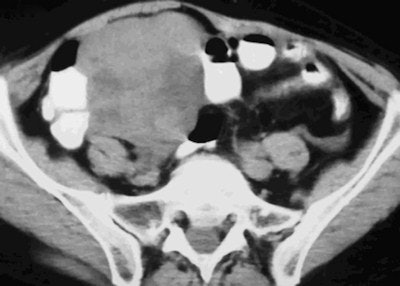

- Hereditary breast-ovarian cancer syndrome is mainly associated with ovarian high-grade serous carcinomas, which seem to arise in the fallopian fimbriae and have better prognosis than sporadic cancers.

- Lynch syndrome predisposes a patient to endometrial cancer, at a lower rate than ovarian cancers. Endometrial cancers show a predilection for the lower uterine segment and tend to be histologically more diverse in contrast to their sporadic counterparts, including nonendometrioid carcinomas. Ovarian cancers related to Lynch syndrome and Cowden syndrome are mostly of the nonserous type, usually endometrioid.